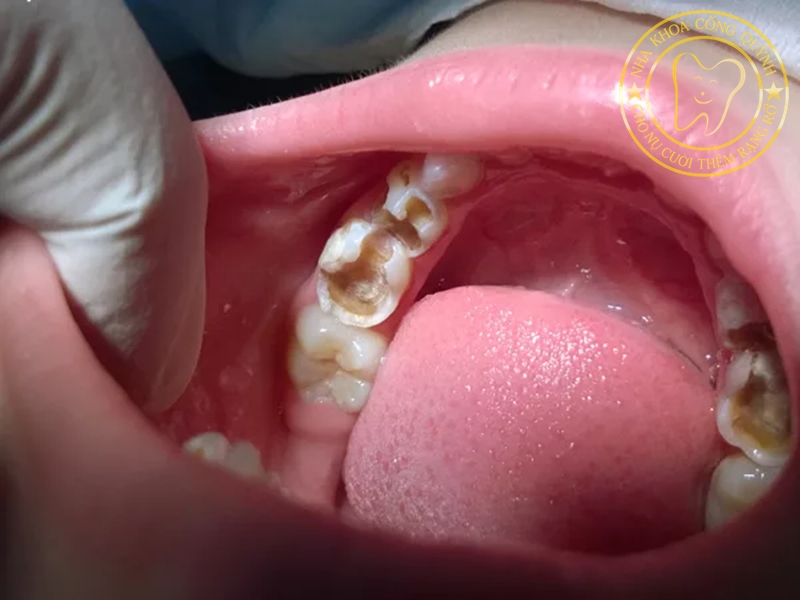

Câu trả lời là: CÓ. Trám răng sữa là phương pháp phục hồi phần răng bị tổn thương bằng vật liệu nha khoa chuyên dụng, giúp:

Ngăn ngừa viêm tủy, viêm nướu và nhiễm trùng

Răng sữa bị sâu nhẹ, chưa ảnh hưởng đến tủy